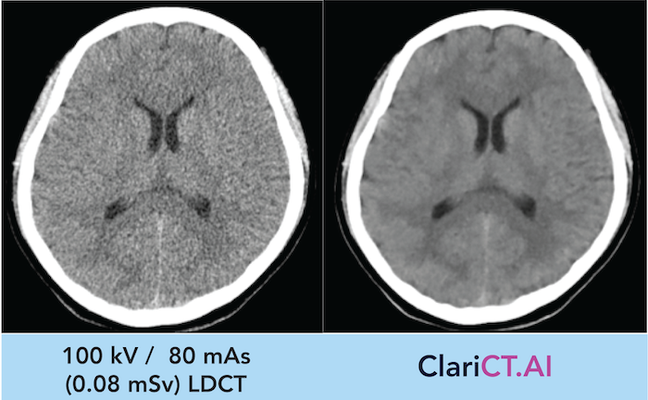

ClariCT.AI es el primer motor de claridad para TC potenciado por inteligencia artificial. Su tecnología de aprendizaje profundo ha sido entrenada con más de un millón de imágenes médicas, lo que le permite identificar miles de patrones de ruido en estudios de baja o ultrabaja dosis. A diferencia de los métodos tradicionales, ClariCT.AI realza las estructuras anatómicas sin generar distorsiones ni apariencia plástica, manteniendo una imagen natural y clínicamente útil.

Mejora la claridad de imagen en estudios de TC con dosis ultrabaja, incluso en casos no diagnósticos.

Elimina el ruido cuántico sin distorsionar la textura natural ni generar apariencia plástica.

ClariCT.AI ha demostrado una reducción de ruido de hasta el 92%, incluso en estudios con dosis tan bajas como 3 mAs.

Radiólogos han validado su eficacia en más de 160 casos clínicos, destacando mejoras significativas en la visibilidad de estructuras pulmonares, abdominales, cardíacas y cerebrales.